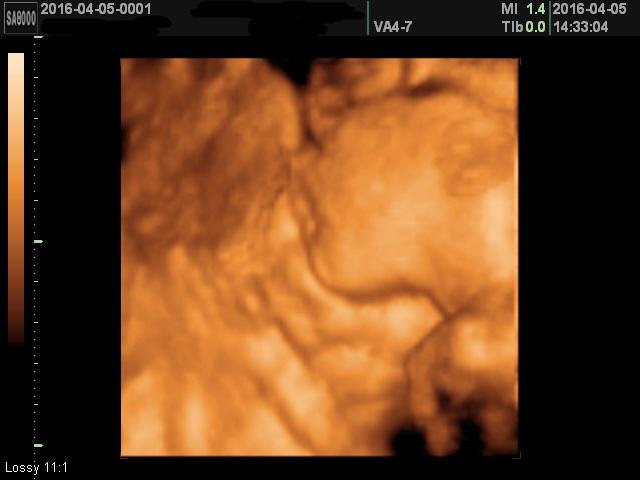

Sziasztok, jöttem beszámolni hátha erre jár még valaki  minden rendben van Babókával, méhlepénnyel, köldökzsinórral, és hoztam egy "olyanédeskisnyakonpuszilnám" képet a Legkisebb Fiúnkról: